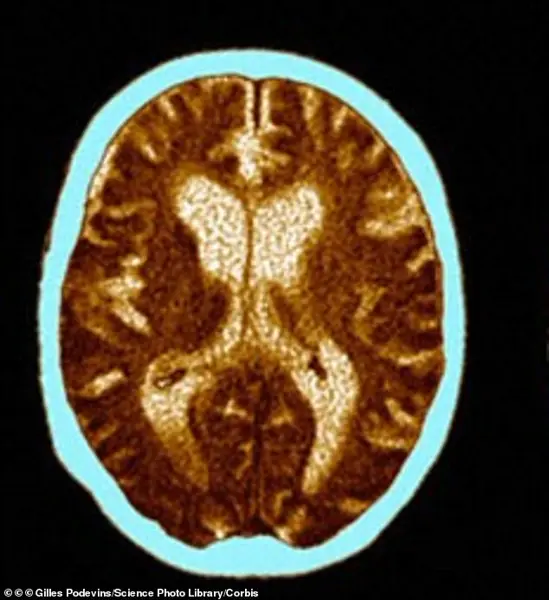

Brain imaging revealed significant atrophy, particularly in regions critical for memory and executive function, underscoring the irreversible damage caused by the disease.